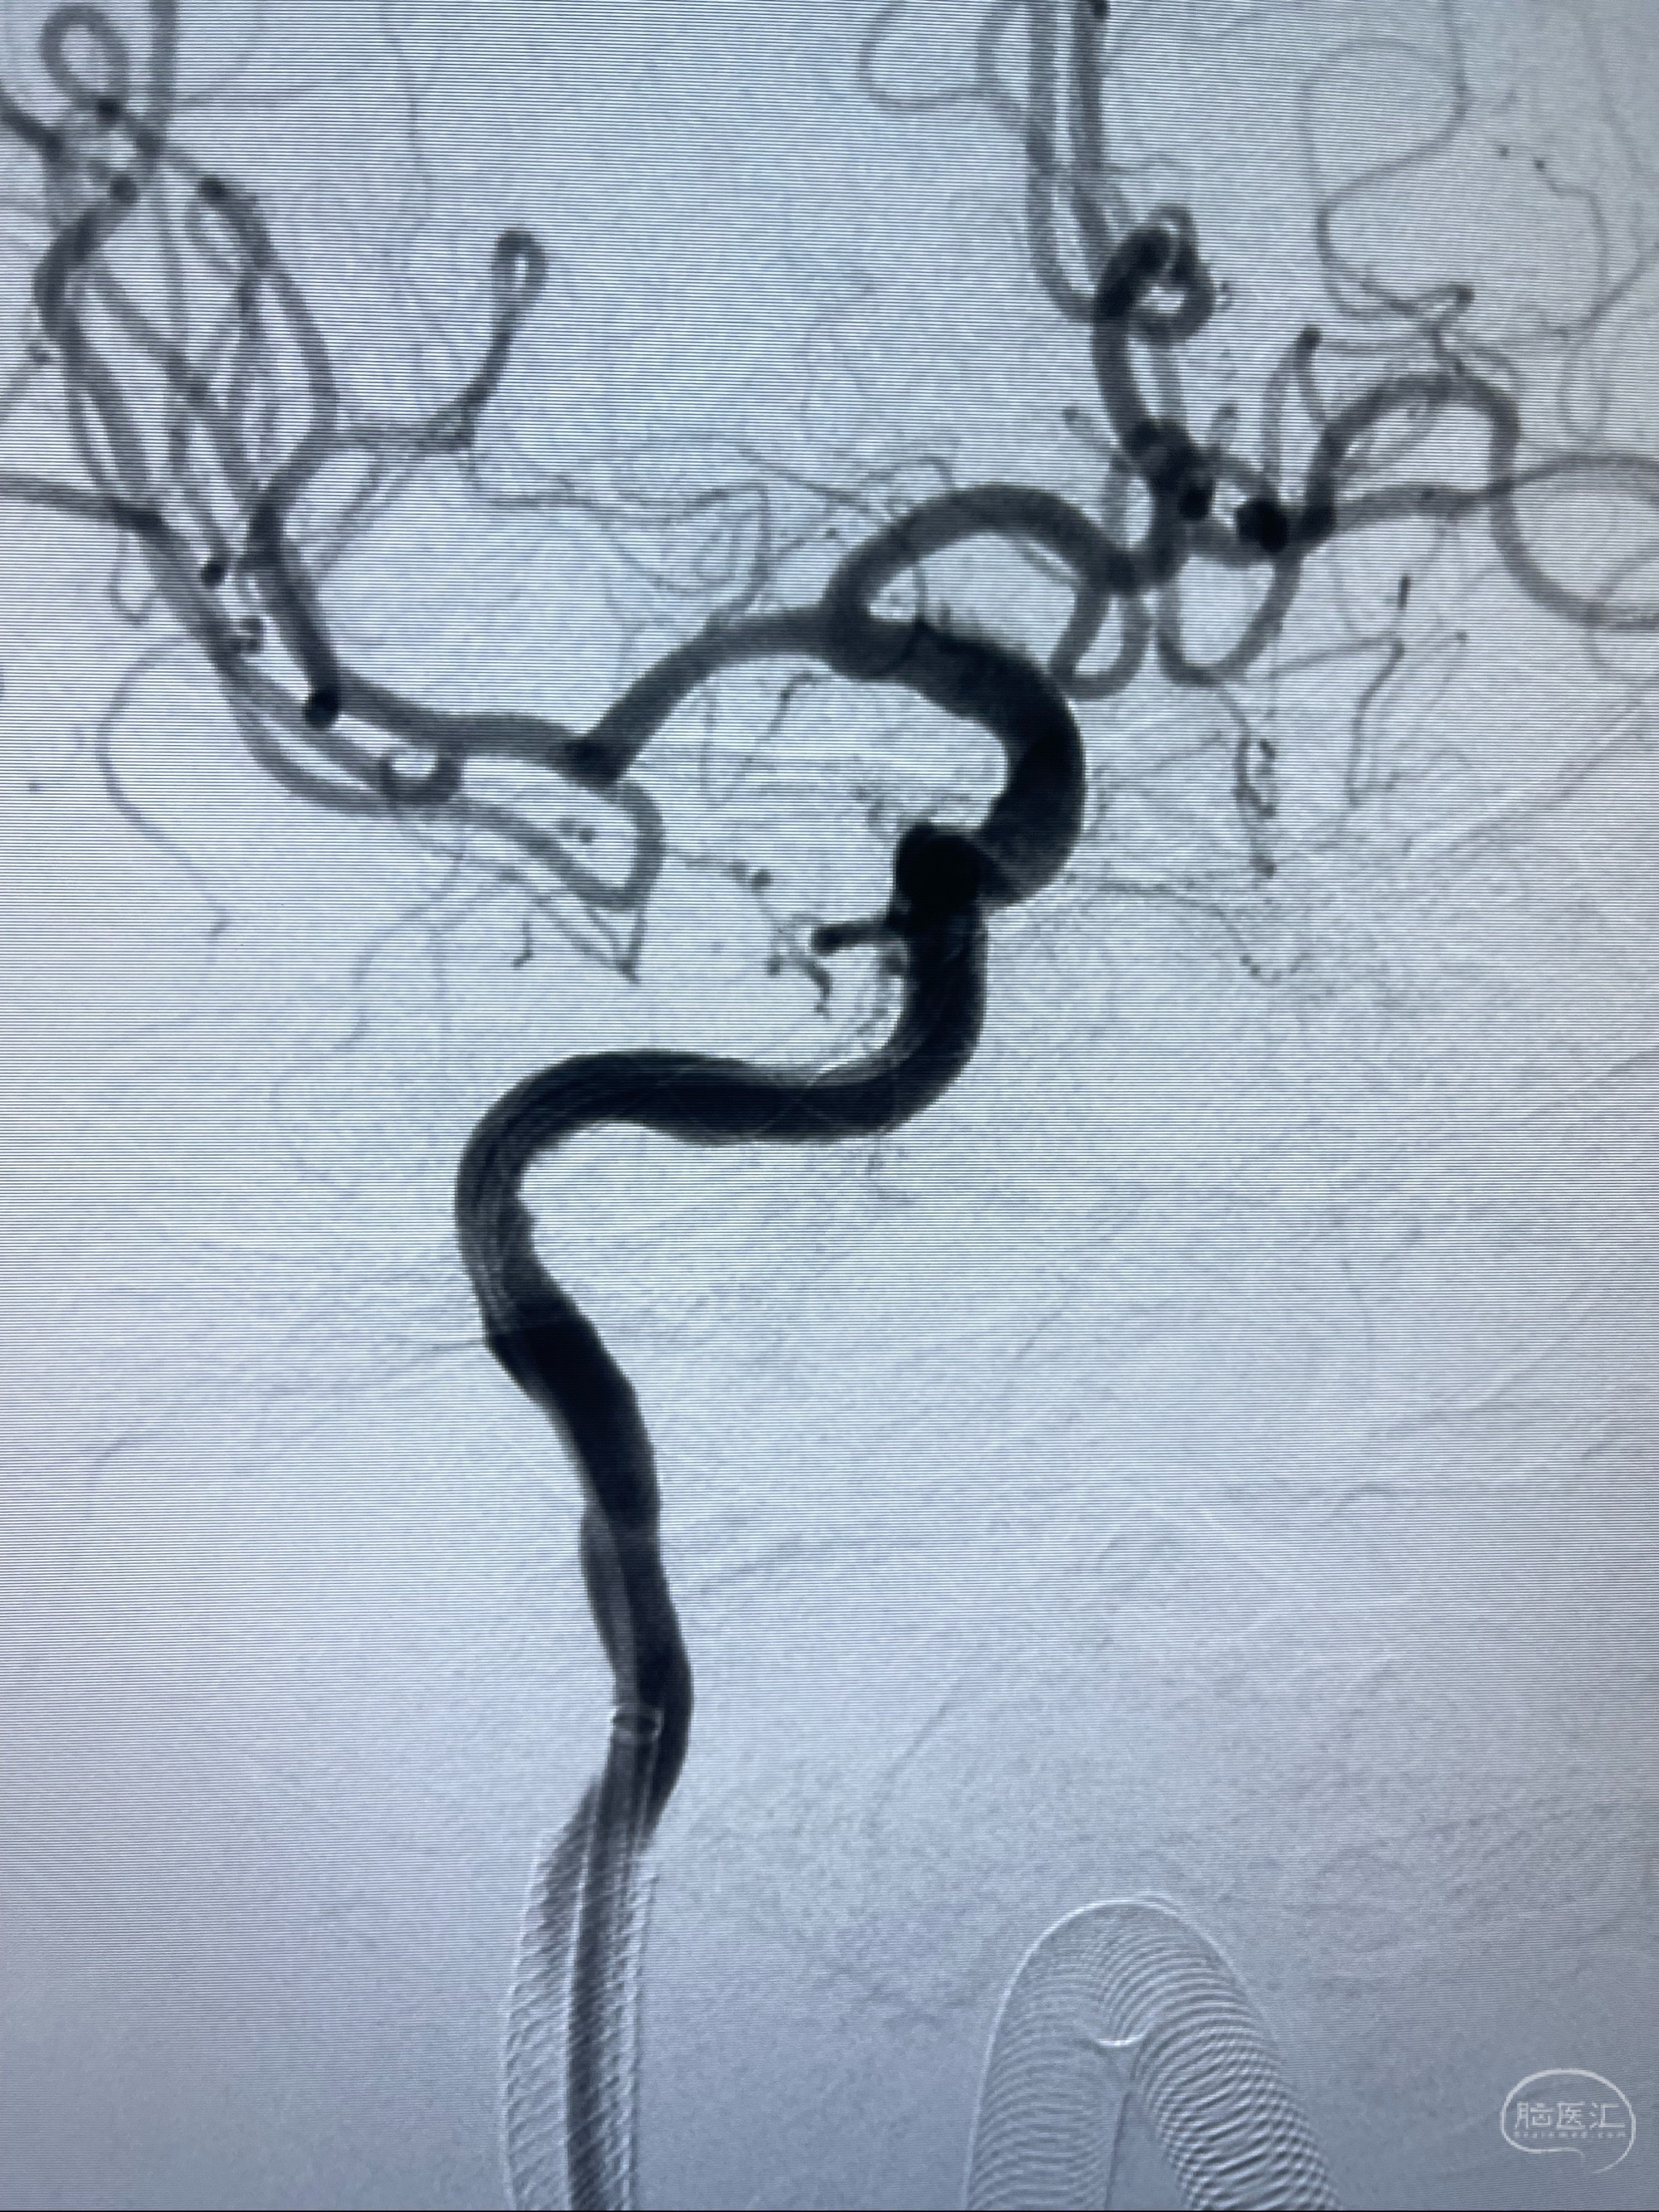

路径图下,5.5-50mmLeo支架导管在微导丝引导下超选择性插入远段Leo支架内

两枚支架部分重叠

多次确认支架位置及打开贴壁情况

支架完全打开,近心端位于原颈动脉支架远心端内

麻醉苏醒佳,遵嘱活动!

术后给予替罗非班300ug/h维持,序贯阿司匹林100mg➕泰嘉75mg口服